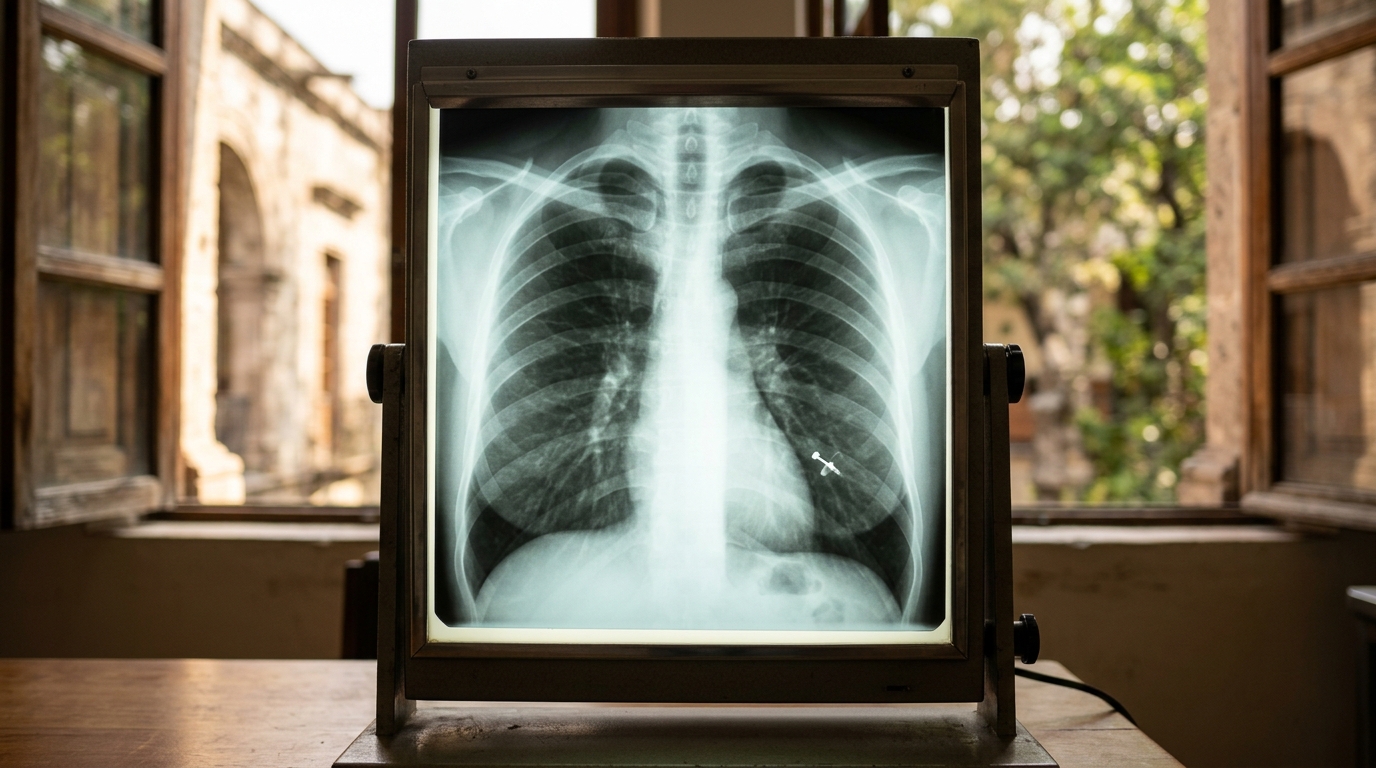

멕시코 여성 모니카 데야니라 카브레라 바라하스(26)는 처음엔 지속된 기침을 날씨 변화 때문으로 생각했다. 하지만 증상이 한 달 이상 나아지지 않자 병원을 찾아 정밀 검사를 받았다. 검사 결과, 자신이 잃어버린 줄도 몰랐던 코 피어싱이 폐 안에 들어가 있는 것을 확인했다.

의료진은 잠든 사이 피어싱이 떨어졌고, 등을 대고 누운 상태에서 이를 흡입했을 가능성이 크다고 추정했다. 그녀는 평소 여러 개의 피어싱을 하고 있었기 때문에 코 피어싱이 빠진 사실을 인지하지 못했을 것으로 보였다. 피어싱 제거 시술은 예상보다 복잡했다. 피어싱이 기관지 내부 조직에 일부 붙어 있어 시술이 1시간 20분 이상 진행되었고, 완전히 제거하는 데 실패했다. 이후 수술이 필요했다.